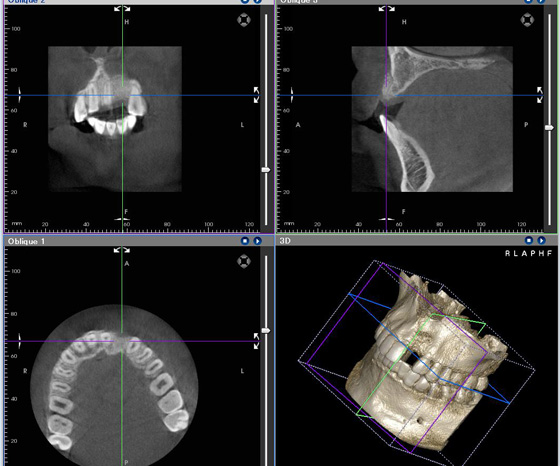

●インプラント(上顎)

上顎の歯がなく、インプラントにて機能回復を行ったケースです。

GBR(骨誘導再生)

あごの骨の高さや幅が少ないと、そのままではインプラント治療はできません。

GBR法は主にそういったケースでもインプラントの植立が可能になるように骨を再生させる(造る)方法です。

この方法は、手術により遮断膜を歯肉の下に入れ骨の再生するスペースを作ってやります。このスペースがないと歯肉の再生のスピードが速いため、歯肉が入り込み、骨の再生ができません。そして、このスペースに骨補填材填入や親知らずの周りの骨などを移植し、骨を再生(造る)します。

この方法により、今まで困難だった骨量が少ないところにもインプラント治療が可能になりました。

サイナスリフト

歯が抜けて時間が経過等で顎の骨がやせてしまい、インプラントを入れるスペースが不足する事があります。

以前は骨がやせているとインプラントができないケースがありましたが、骨の厚みを作るため「上顎洞(サイナス)」洞底部に骨再生を施すことでインプラントが可能になりました。

サイナスリフトは、上顎の臼歯部あたりの骨が薄くインプラント治療を選択できない方に、自家骨や骨補填材を利用する方法(自家骨や骨補填材を利用しない場合もあります)でインプラントを埋め込むのに十分な骨の厚みを確保します。